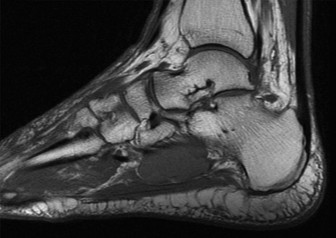

Figure 2: Coronal T1-weighted MRI image from the same patient, highlighting the comminution of the talar neck and body, and involvement of the subtalar joint. The image further elucidates the articular damage and subchondral bone changes not fully appreciated on plain radiographs or CT.

• Articular Cartilage Assessment: While CT shows bone, MRI sagittal views exquisitely demonstrate the integrity of the articular cartilage. We observed areas of chondral bruising and early subchondral edema on the talar dome, consistent with impaction. Furthermore, articular step-offs and incongruity in both the tibiotalar and subtalar joints were precisely quantified, guiding the need for meticulous anatomical reduction.

• Talar Head and Neck Morphology: The sagittal images provided a detailed profile of the fracture lines through the talar neck and body, allowing for precise measurement of anterior, posterior, and superior displacement and angulation. This was critical for understanding the extent of shortening and the specific vector required for reduction. They also helped identify small, non-displaced fracture lines or occult fractures that might be missed on CT, particularly in areas of complex anatomy.

• Subtalar Joint Involvement: The sagittal plane is paramount for evaluating the posterior facet of the subtalar joint. In our patient, the fracture clearly extended into this joint, with significant displacement of the posterior talar facet, highlighting the necessity for accurate reduction of this weight-bearing surface to prevent post-traumatic arthrosis.